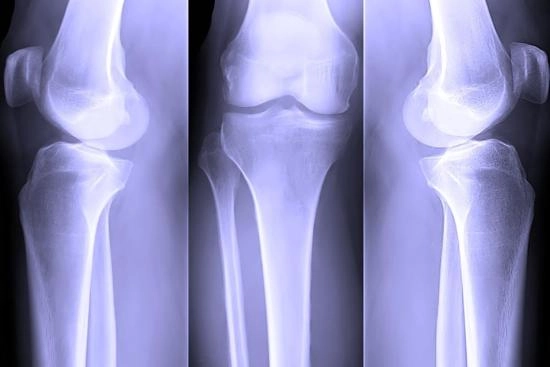

تستغرق هذه الإجراءات العلاجية حوالي 6 أسابيع للشفاء ولكن إذا استمرت الآلام وصعوبة تحريك الركبة، يقوم الدكتور ياسر رضا بإجراء تصوير الرنين المغناطيسي لفحص حالة الركبة؛ وفي الحالات المتقدمة للغاية، قد يلجأ الطبيب إلى العلاج عبر الوسائل التالية: